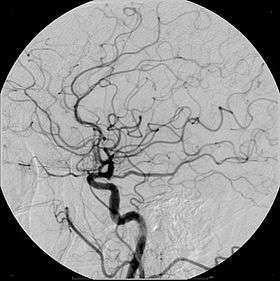

- Angiography (arterial investigations)

Carbon dioxide

Carbon dioxide also has a role in angiography. It is low-risk as it is a natural product with no risk of allergic potential. However, it can be used only below the diaphragm as there is a risk of embolism in neurovascular procedures. It must be used carefully to avoid contamination with room air when injected. It is a negative contrast agent in that it displaces blood when injected intravascularly.